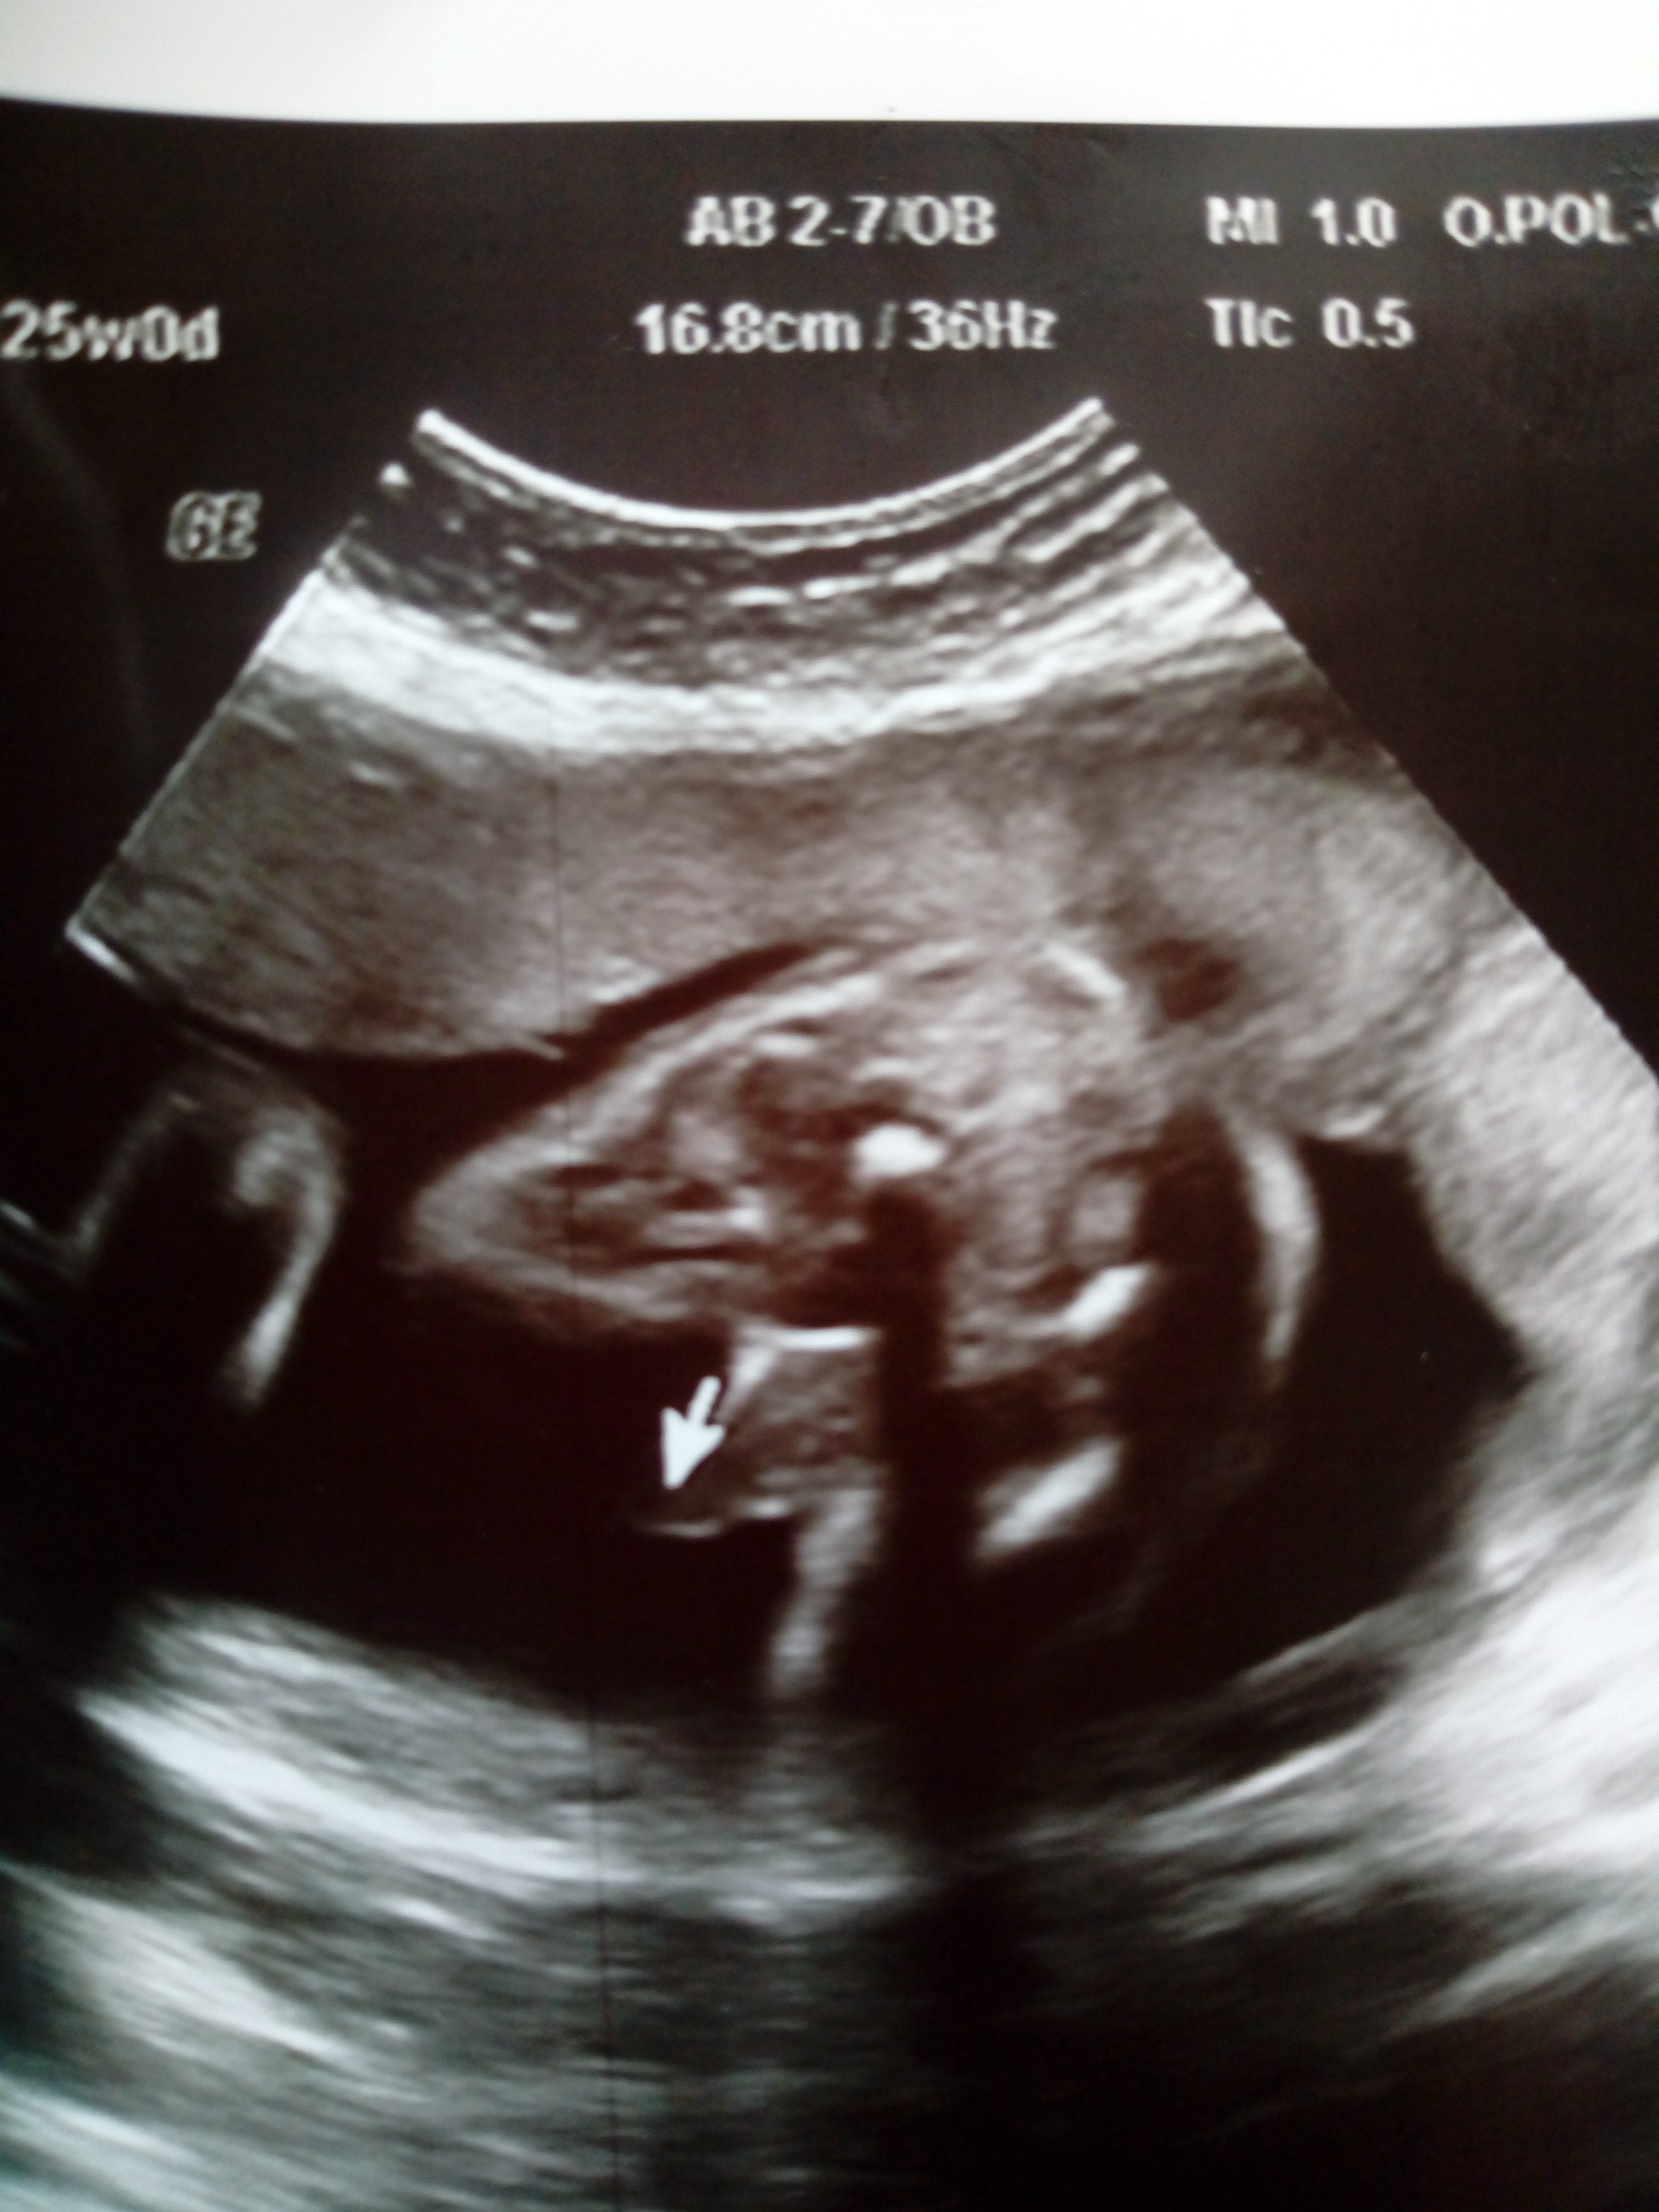

Cześć postanowiłam dodać do was pytanie bo ciekawość mnie zżera...:) 15tc dziewczynka 19tc chyba chłopiec. Pępowina między nóżkami ciężko ocenić ale ostatecznie stwierdzenie że prącie dotyka pępowiny...dodaje dwa ostatnie zdjęcia z USG na drugim to najjaśniejsze białe między nóżkami to pępowina :) jak myślicie róż czy błękit?

Cześć postanowiłam dodać do was pytanie bo ciekawość mnie zżera...:) 15tc dziewczynka 19tc chyba chłopiec. Pępowina między nóżkami ciężko ocenić ale ostatecznie stwierdzenie że prącie dotyka pępowiny...dodaje dwa ostatnie zdjęcia z USG na drugim to najjaśniejsze białe między nóżkami to pępowina :) jak myślicie róż czy błękit?Zobacz załącznik 941612Zobacz załącznik 941613

Nie jest to jakieś mega wyraźne usg, dlatego obstawiałabym dziewczynkę. :)

U syna w 18 tygodniu miałam już widoczny worek mosznowy. Niestety poczekałabym na kolejne usg bo tu nie ma nic pewnego.